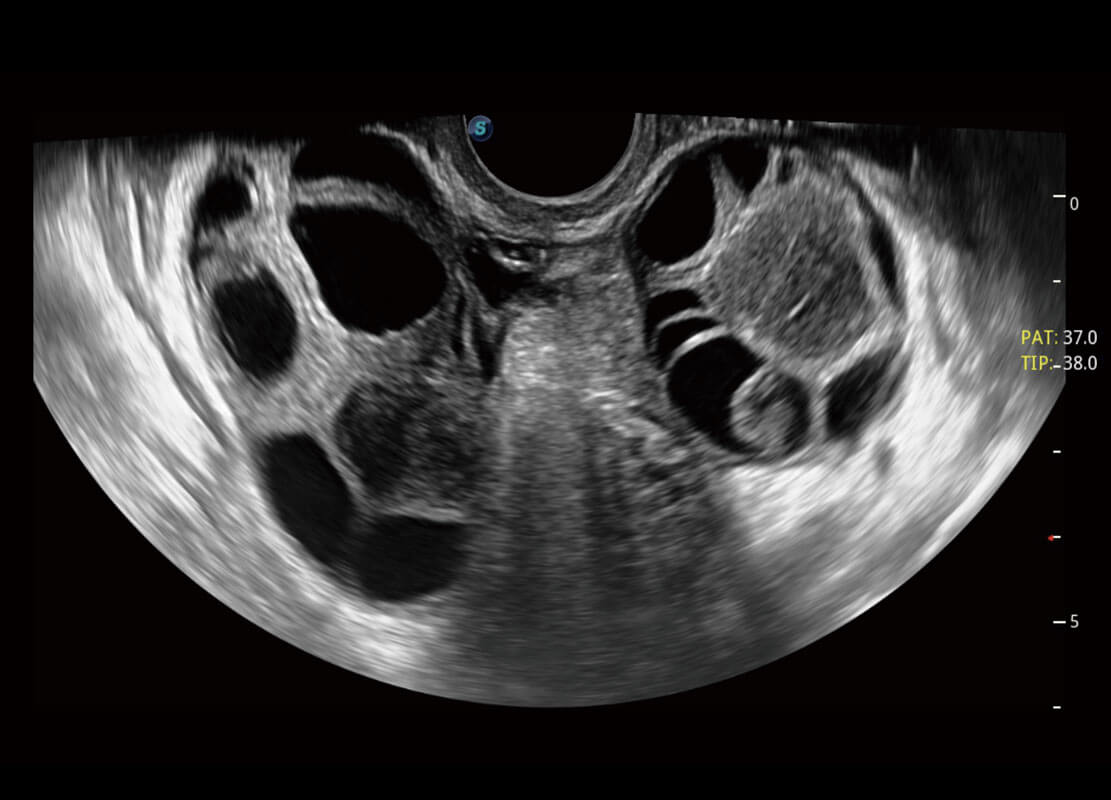

生殖健康

P60优异的图像质量搭载专科探头,在妇科基础疾病的诊断、卵泡生长的监测、输卵管通畅情况的判别等方面为您提供生殖应用方案。

• 腔内妇科-卵巢